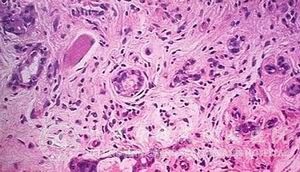

京城皮肤医院的皮肤介绍,汗管瘤作为一种良性肿瘤,它的临床上的组织病理表现为以下几个方面:

1. 形状为圆形,椭圆形或者蝌蚪状;

2. 通过病理检查可在 浅层上发现双层嗜碱性上皮*形成囊腔样结构;

3. 上皮*出现嗜伊红胶样物;